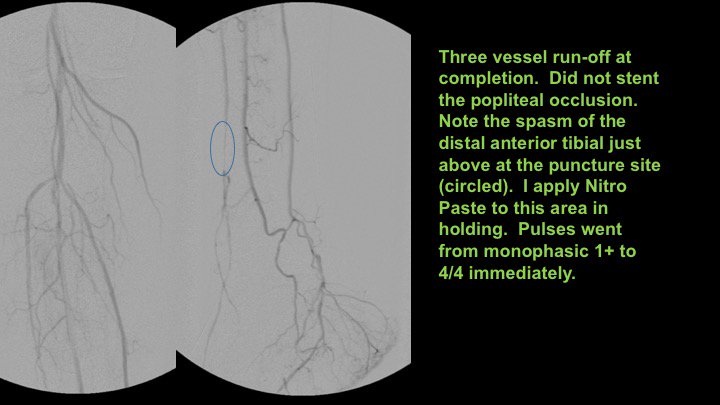

The best example of CTOP IV I've seen clinically. Know the techniques! Procedures failed by others become routine when you understand the pathology. #CLIFighters #MyLegMyLife #Can'tCTOPWon'tCTOP @SOBE_Vascular @kmadass @SDhandMD @Mustapja @FadiSaab17 @LessneVIR @SIR_ECS @SIRRFS